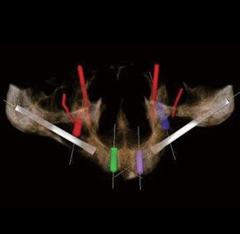

数字化种植是利用计算机图形图像技术,根据口内CT扫描数据以及光学扫描数据在计算机上重建患者颌骨立体模型,医生以此为基础,确定患者种植体嵌入位置、数量、种植深度、角度等,生成科学、精准的导板设计方案,将种植设计准确地转化到手术操作中,最后配上数字化种牙手术专用的手术工具、结合患者自身的情况制作修复体,完成种植治疗。

- 口内模拟种植,避开神经血管,设计种植方案;通过CAD/CAM激光扫描和CBCT检测等, 在计算机上重建患者口腔三维立体模型,凭借由打印技术制作的种植导板对手术全程的精准把控,减少手术时间及手术创伤,实现对缺牙的修复。

在导板辅助下可避免医生经验误差,掌控种植角度和深度,减少创伤,有效避开神经、血管等危险部位。